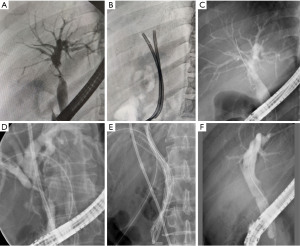

When BS was first diagnosed, 54 (56.3%) patients presented with AS, whereas 42 (43.7%) patients presented with NAS. After radiological re-evaluation, among the 96 patients, 42 (43.8%) were type I, 31 (32.3%) were type II, and 23 (24.0%) were type III. Stent treatment schemes used for the first successful endoscopic treatment were described based on these new classification methods (Figure 2A). Type I patients received FCMS treatment (61.9%) or single-PBS treatment (38.1%). Type III patients received only PBS, including single-PBS (30.4%) or multi-PBS (69.6%). However, patients with type II underwent a variety of treatment options, including multi-PBS (54.8%), FCMS + PBS (19.4%), single-PBS (16.1%) and FCMS (9.7%). To demonstrate the guiding significance of this new classification for treatment options, the stent treatment scheme used in the binary classification system was also described (Figure 2B). For patients with AS, FCMS (50.0%) and single-PBS (31.5%) were the main treatment options. In addition, 11.1% received multi-PBS, and 7.4% received FCMS + PBS. For patients with NAS, multi-PBS (66.7%) and single-PBS (23.8%) were the main treatment options, with 4.8% receiving FCMS and 4.8% receiving FCMS + PBS. Compared to the binary classification system, stent treatments in the new classification were more fixed, especially for type I and type III patients. Endoscopic images of the unique FCMS + PBS implantation scheme and the PBS implantation scheme used for type II patients are shown in Figure 3.

On the premise that an extrahepatic BS with a hepatic confluence of greater than 2 cm is defined as type I, perihilar BS should be regarded as another independent type that differs from intrahepatic BS. Because the high position of the perihilar BS is not suitable for implantation of the FCMS alone, we attempted to insert the FCMS across the narrowed segment, extend it into the left hepatic duct, and insert the PBS on the other side to prevent obstruction (Figure 3F). Notably, this patient did not experience any complications after this procedure and demonstrated a good treatment response during 6 months of follow-up. For five patients who received FCMS + PBS implantation, this treatment showed excellent therapeutic effects. In previous studies, the combined use of FCMS and PBS has been shown to reduce the incidence of complications associated with FCMS (25). In this study, compared with PBS, FCMS + PBS resulted in fewer treatment sessions and lower treatment costs for type II patients. We believe that this is a potentially effective treatment because the FCMS extends beyond the hepatic confluence and the stricture segment, whereas the PBS is inserted into the contralateral secondary bile duct. However, due to the limited number of patients, the effectiveness and safety of this approach still need to be verified in a larger sample. The boundary between type II and type III is the opening of the secondary bile duct, as FCMS cannot be implanted for further treatment.